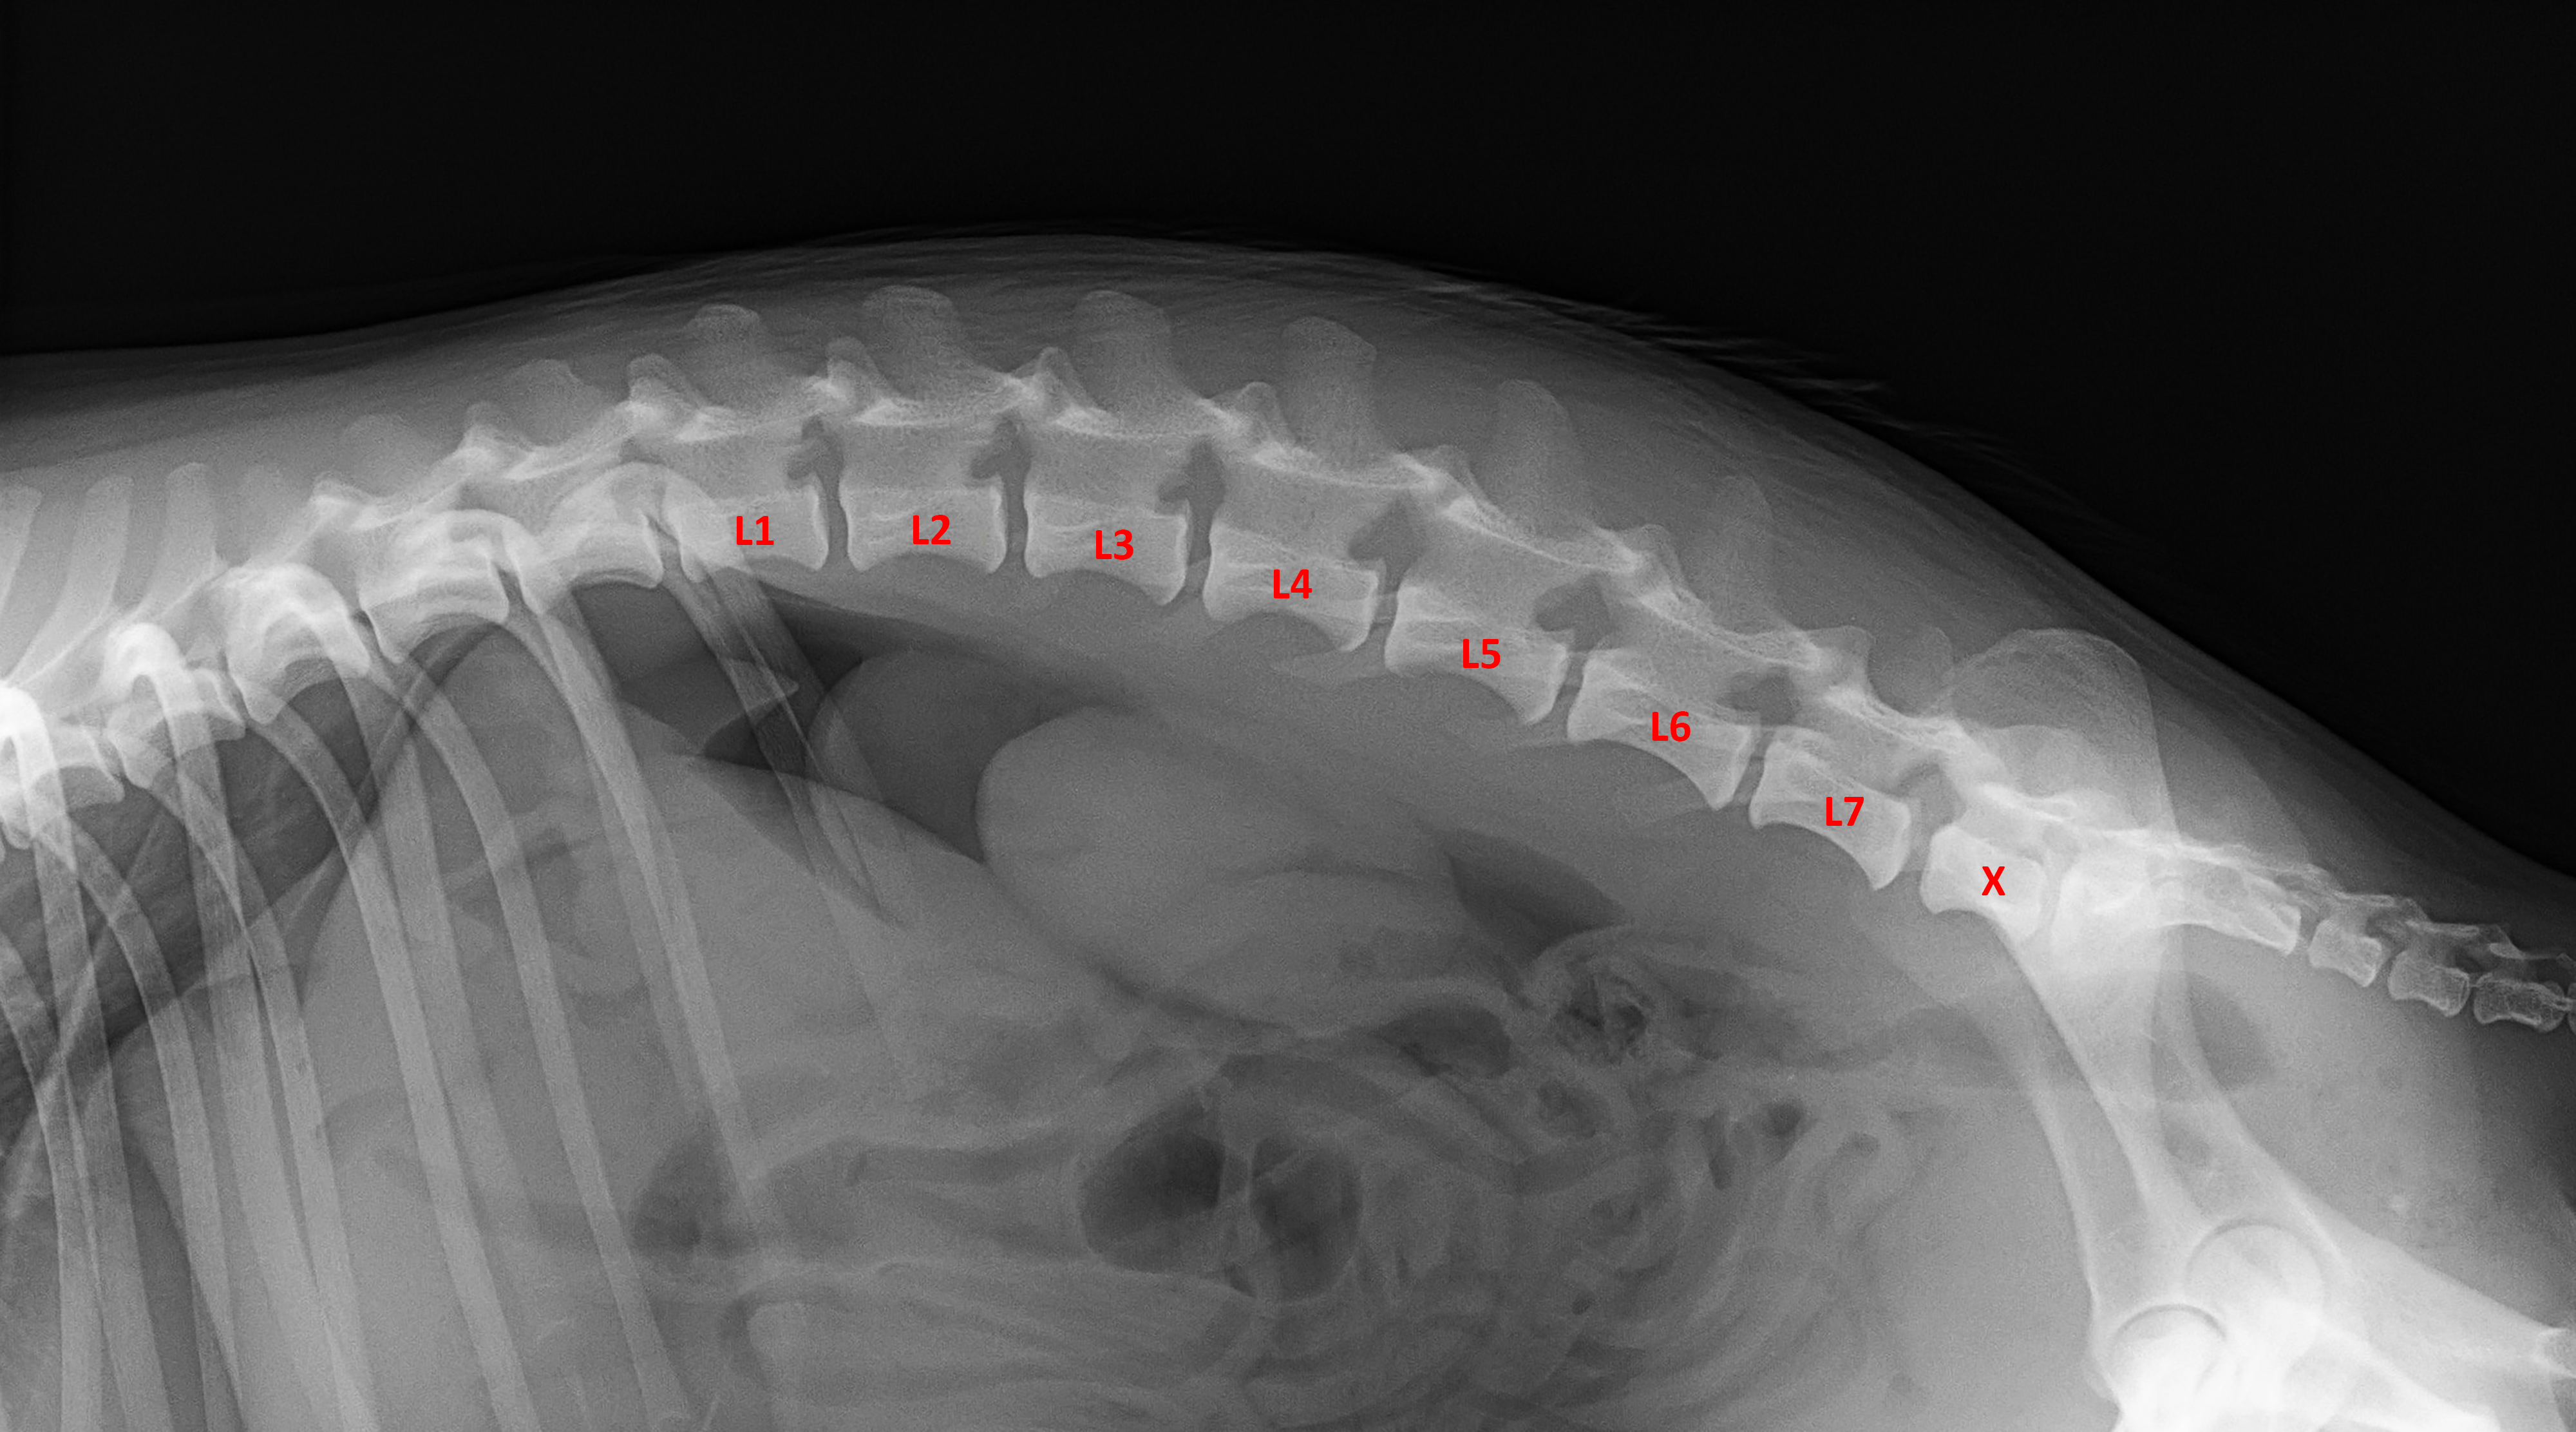

MVDr. Meloun: Lumbosakrální přechodový obratel